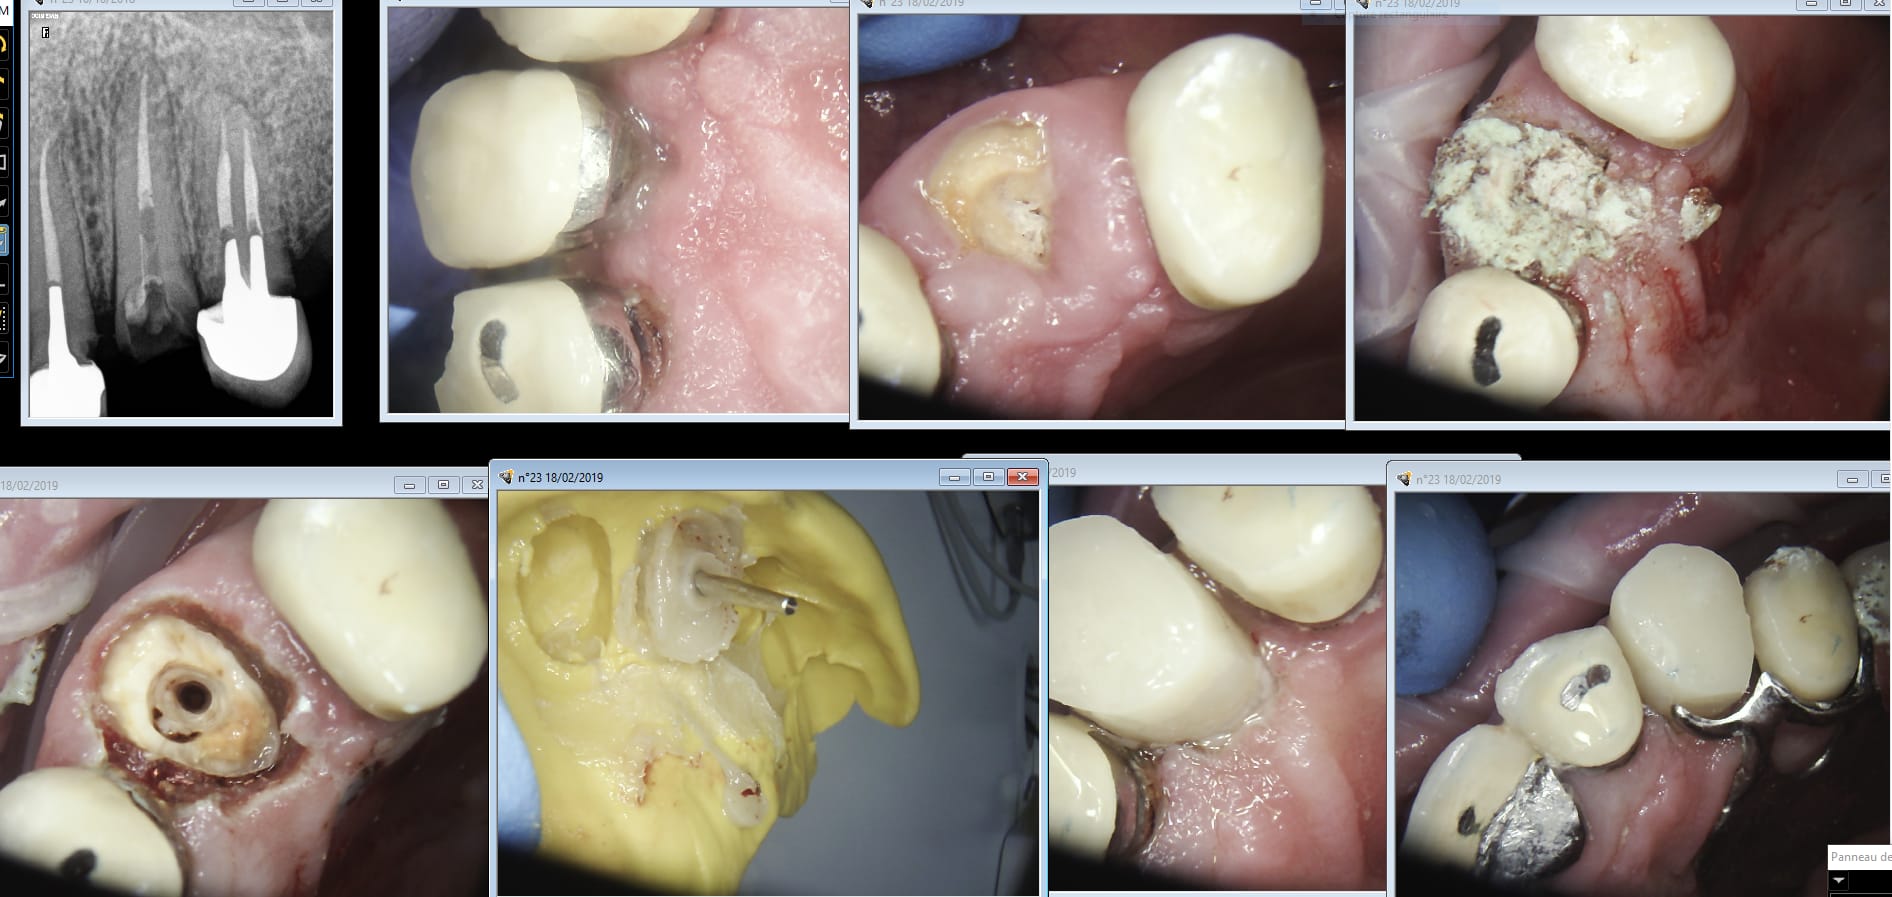

Prothèses chinoises et caméras Coréennes. Couple gagnant dans un exercice en environnement hostile. Vive la république vive la France. -)))

Plus facile avec une camera en plus tu gardes pas le stellite. Et euh silicone français? Lequel ? -)))